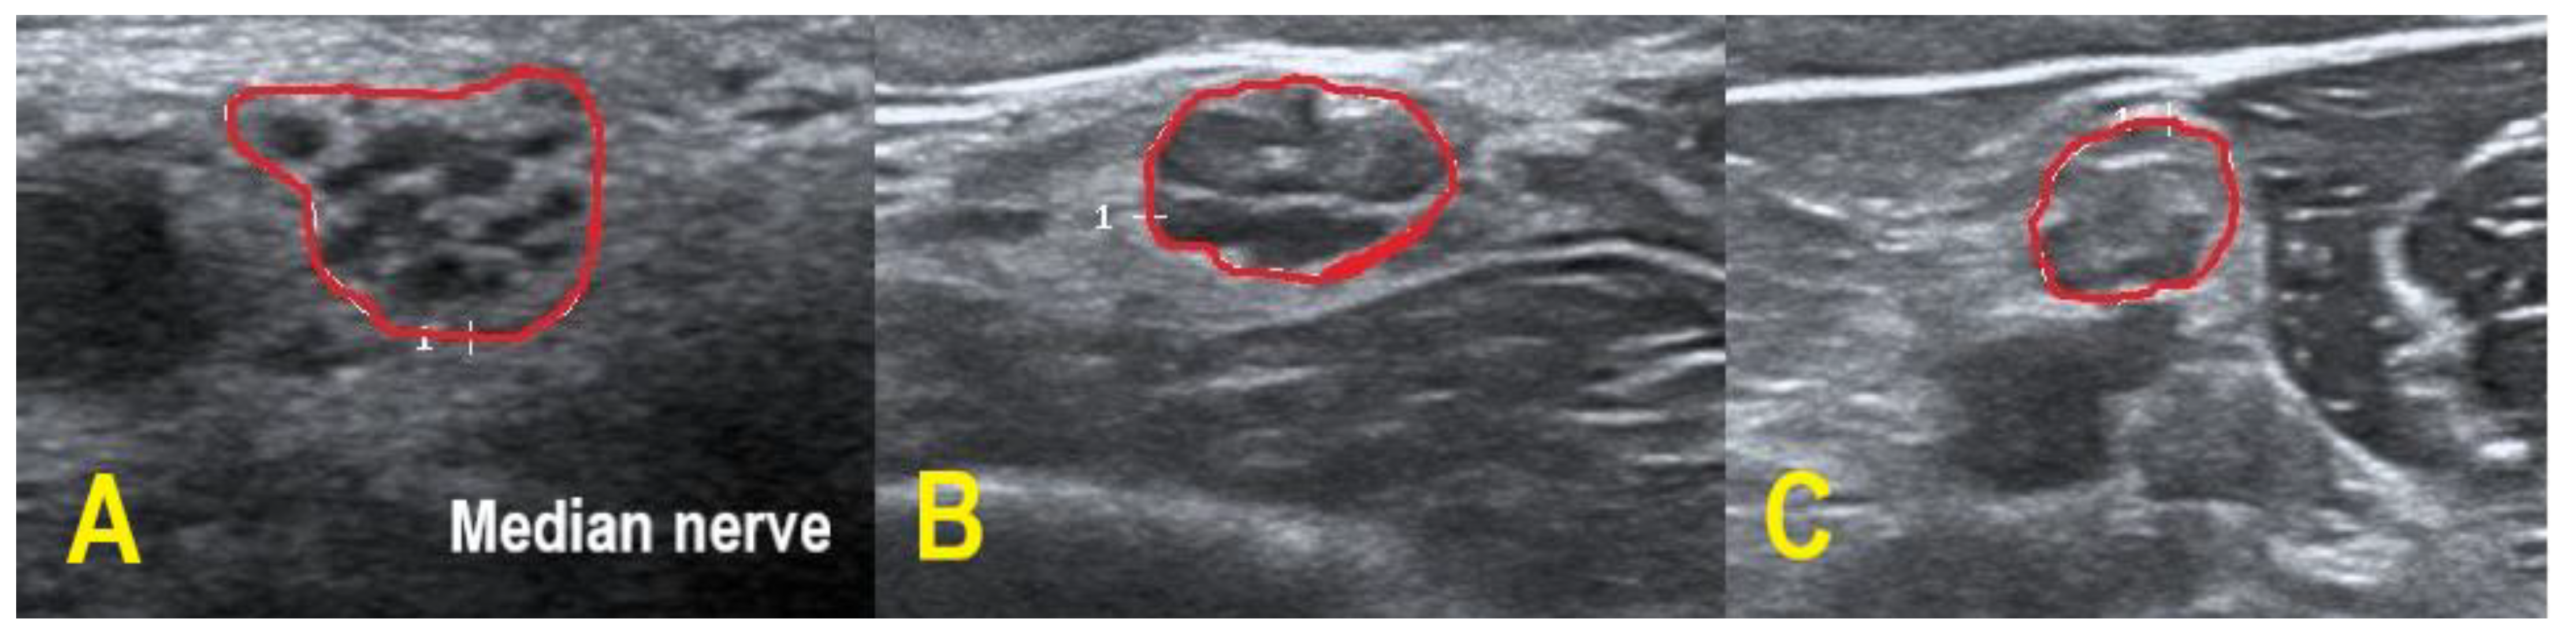

POEMS patients demonstrated overt homogeneous (two patients) and regional enlargement (one patient) in the median nerve, while CIDP patients had overt homogeneous (five patients), inhomogeneous (two patients), regional (two patients) and mild homogeneous (one patient) enlargement patterns. HRUS findings of the right median nerve in POEMS syndrome patient #3 are shown in Figure 2. Enlargement patterns in the ulnar nerve were equally heterogeneous. Two POEMS syndrome patients exhibited inhomogeneous and another mild homogeneous enlargement, five CIDP patients had overt homogeneous, two inhomogeneous, one mild homogeneous and one regional enlargement (and also one patient without an enlargement pattern).

Figure 2. HRUS in POEMS syndrome patient #3. HRUS demonstrated overt homogeneous enlargement of the CSA in the right median nerve (within red border; CSA up to 2.0-fold increased). Axilla (a): CSA 20 mm². Upper arm (b): 25 mm². Midarm (c): 23 mm². Forearm (d): 15 mm². Of note, the intraneural echointensity reflects hyperechoic interfascicular tissue next to hypoechoic fascicles.